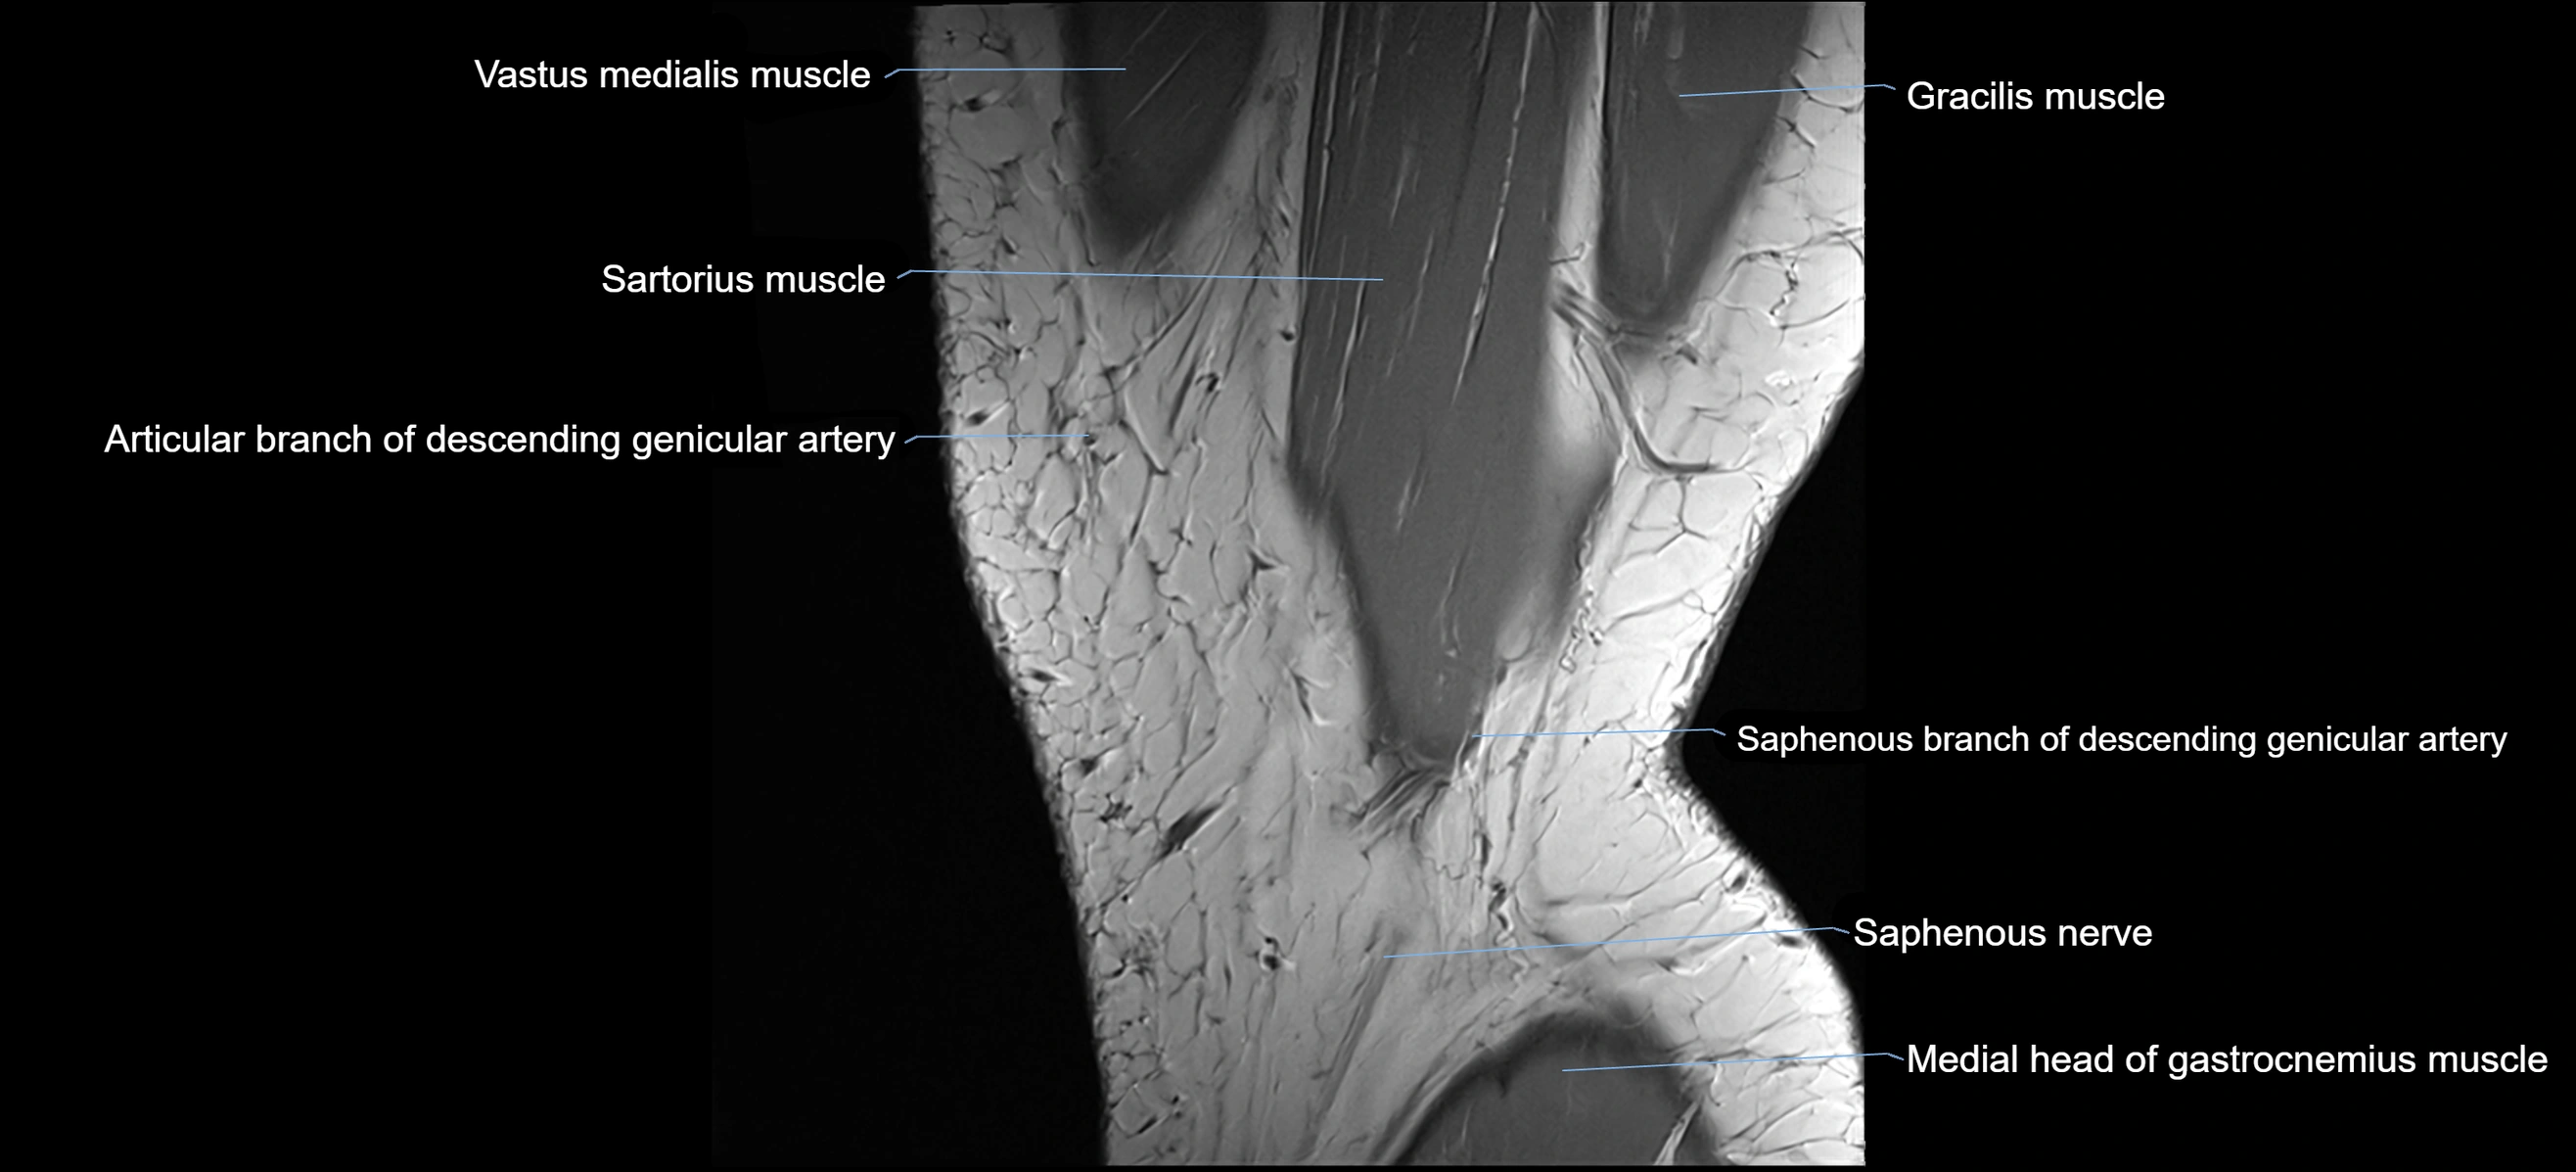

- Descending genicular artery (Saphenous branch)

- Infrapatellar branch of saphenous nerve

- Medial head of gastrocnemius muscle

- Saphenous nerve

- Sartorius muscle